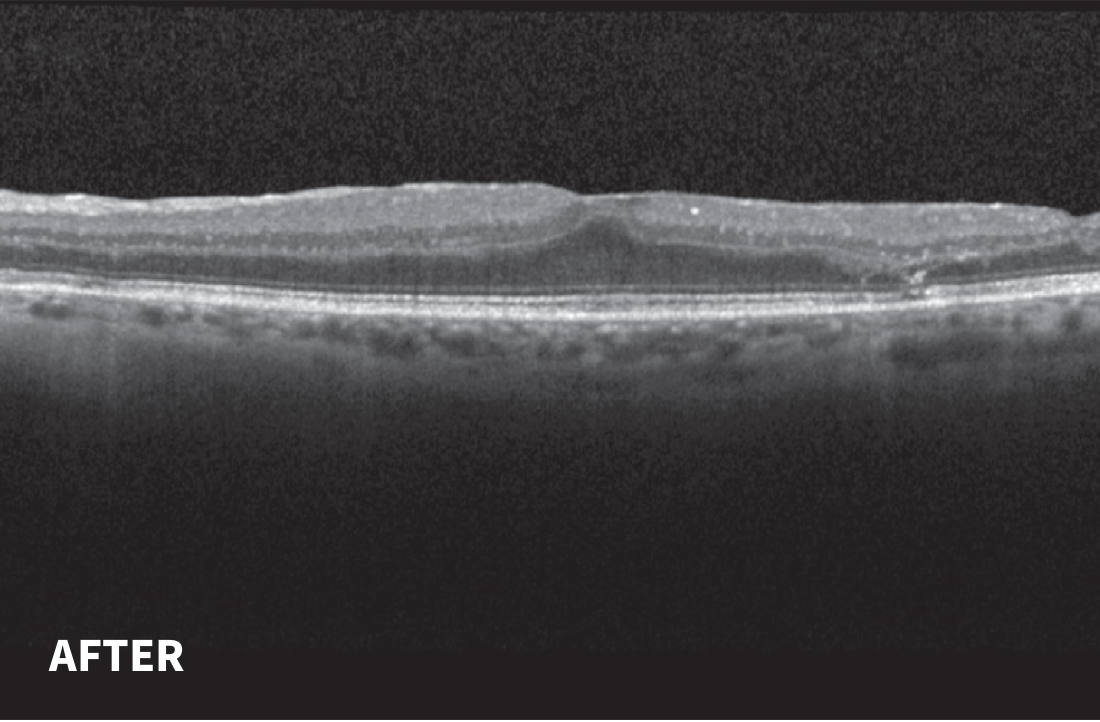

<p>Figure 2. After 9 Months YUTIQ Treatment OS: OCT</p>

Figure 2. After 9 Months YUTIQ Treatment OS: OCT

Nine Months Follow-up After YUTIQ Treatment

No interval follow-up due to COVID-19; CME resolved with improvement in visual acuity